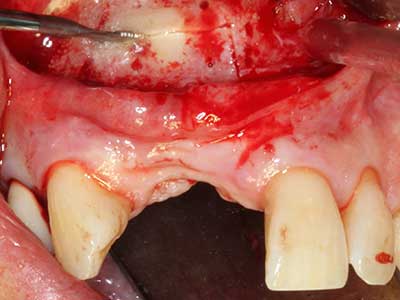

Пиезохирургията има допълнителни предимства при събиране на костни блокове. В допълнение към високата прецизност при остеотомията, описана по-горе, употребата на фините режещи накрайници значително намаляват загубата на материал. Голяма загуба на материал по време на събиране може да се очаква с дебелите накрайници, особено при употреба на борери Линдеман (Lakshmiganthan, Gokulanathan et al. 2012). Базалното разделяне, което е необходимо, особено за присадка на блок при ретромолар, е улеснено от специално създадени правоъгълни триони. В резултат на това, пиезохирургията е разглеждана като прецизна, улеснена и безопасна процедура за събиране на костни блокове в ретромоларното пространство (Happe 2007) (Фиг. 1-12).

Костната тъкан е не само минерализирана структура, тя съдържа и съществено количество колагенови влакна. Това означава, че тя има не само добра компресивна сила, но и известна степен на гъвкавост, която може да се възприеме като предимство при извършване на костна аугментация. В класическата процедура по разширяване чрез костно разделяне, атрофиралият алвеоларен гребен е разделен надлъжно и внимателно разширен след достигане на подходящата остеотомна дълбочина (Фиг. 13-16), в идеалния случай без допълнително отстраняване на периостеума (Brugnami, Caiazzo et al. 2014, Stricker, Fleiner et al. 2014). Системите с винт и пластини с увеличаване на разстоянието при разширяване са доказали ефективността си при разделяне на двете костни ламели, оставайки под прага на фрактурите. В общи линии, оставащата ширина на костта от поне 3–4 mm е задължителна (Chiapasco, Zaniboni et al. 2006), за да се гарантира добра гъвкавост и достатъчно костно покритие за бъдещото поставяне на импланти. Ако е необходимо, вертикалната остеотомия на едната или двете страни може да подобри гъвкавостта. Комбинацията с допълнителни техники за аугментация, особено в букалната страна, е описана като алтернатива на класическата техника.

Процедурата по разделяне е атравматична и няма голяма загуба на пространство, използвайки пиезотриони, и няма значителна разлика между импланти в разделени челюсти и импланти в алвеоларния гребен без костен дефицит (Chiapasco, Zaniboni et al. 2006, Danza, Guidi et al. 2009). Въпреки това, важно е да има достатъчно и продължително охлаждане, особено при ограничено и дълбоко разделяне, за да се избегне термичен стрес в апикално-остеотомните зони.